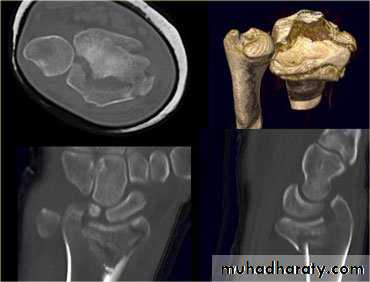

Comminuted colles fracture:

Fracture- sublaxation of the radiocarpal joint: (Barton's fracture)

Volar or dorsal sublaxation,Treatment : undisplaced fracture: casting below elbow for 6wks.

Displaced fracture: open reduction and internal fixation.